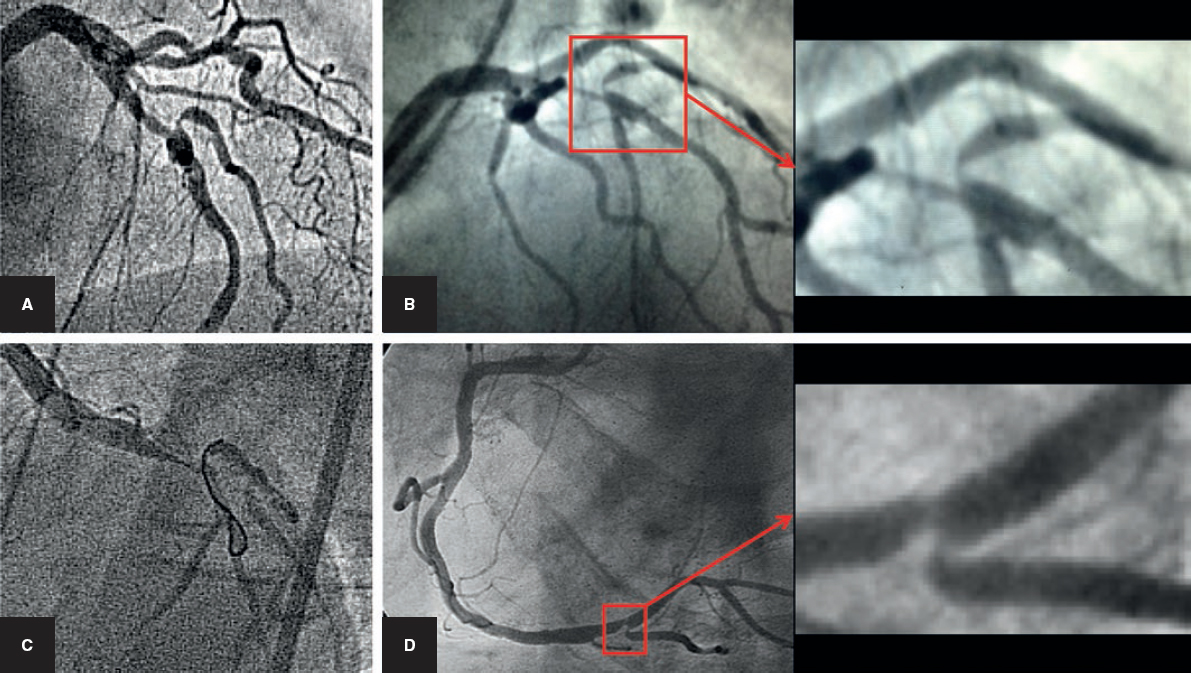

Selective Coronary Artery Fistula Embolization with Hystoacryl During Percutaneous Coronary ...

Large Spontaneous Coronary Artery-to-Right Ventricular Fistula | Journal of Invasive Cardiology